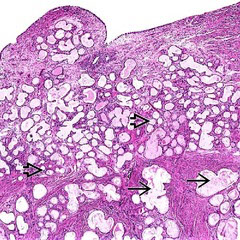

Tunnel clusters

Common, b9, incidental, assoc c multiple prior pregnancies, close to endocervical canal

- caused by localized prolif of endocervical glands c side channels growing out through them

Type A (non-cystic): well-circumscribed, pseudoinfiltrative, oval to pointed gland lumens, smaller cuboidal amphophilic or mucinous columnar, c big nuclei c mild nuclear atypia, florid glandular hyperplasia, and big nucleoli, minimal mits

- assoc c type B

Type B (cystic): larger glands c cystic dilation arranged in lobules, lined by bland flat to cuboidal cells c no mits

Micro: looks b9 c minimal atypia

IHC: (+)

- negative intracytoplasmic CEA

Tunnel clusters

Type B tunnel clusters